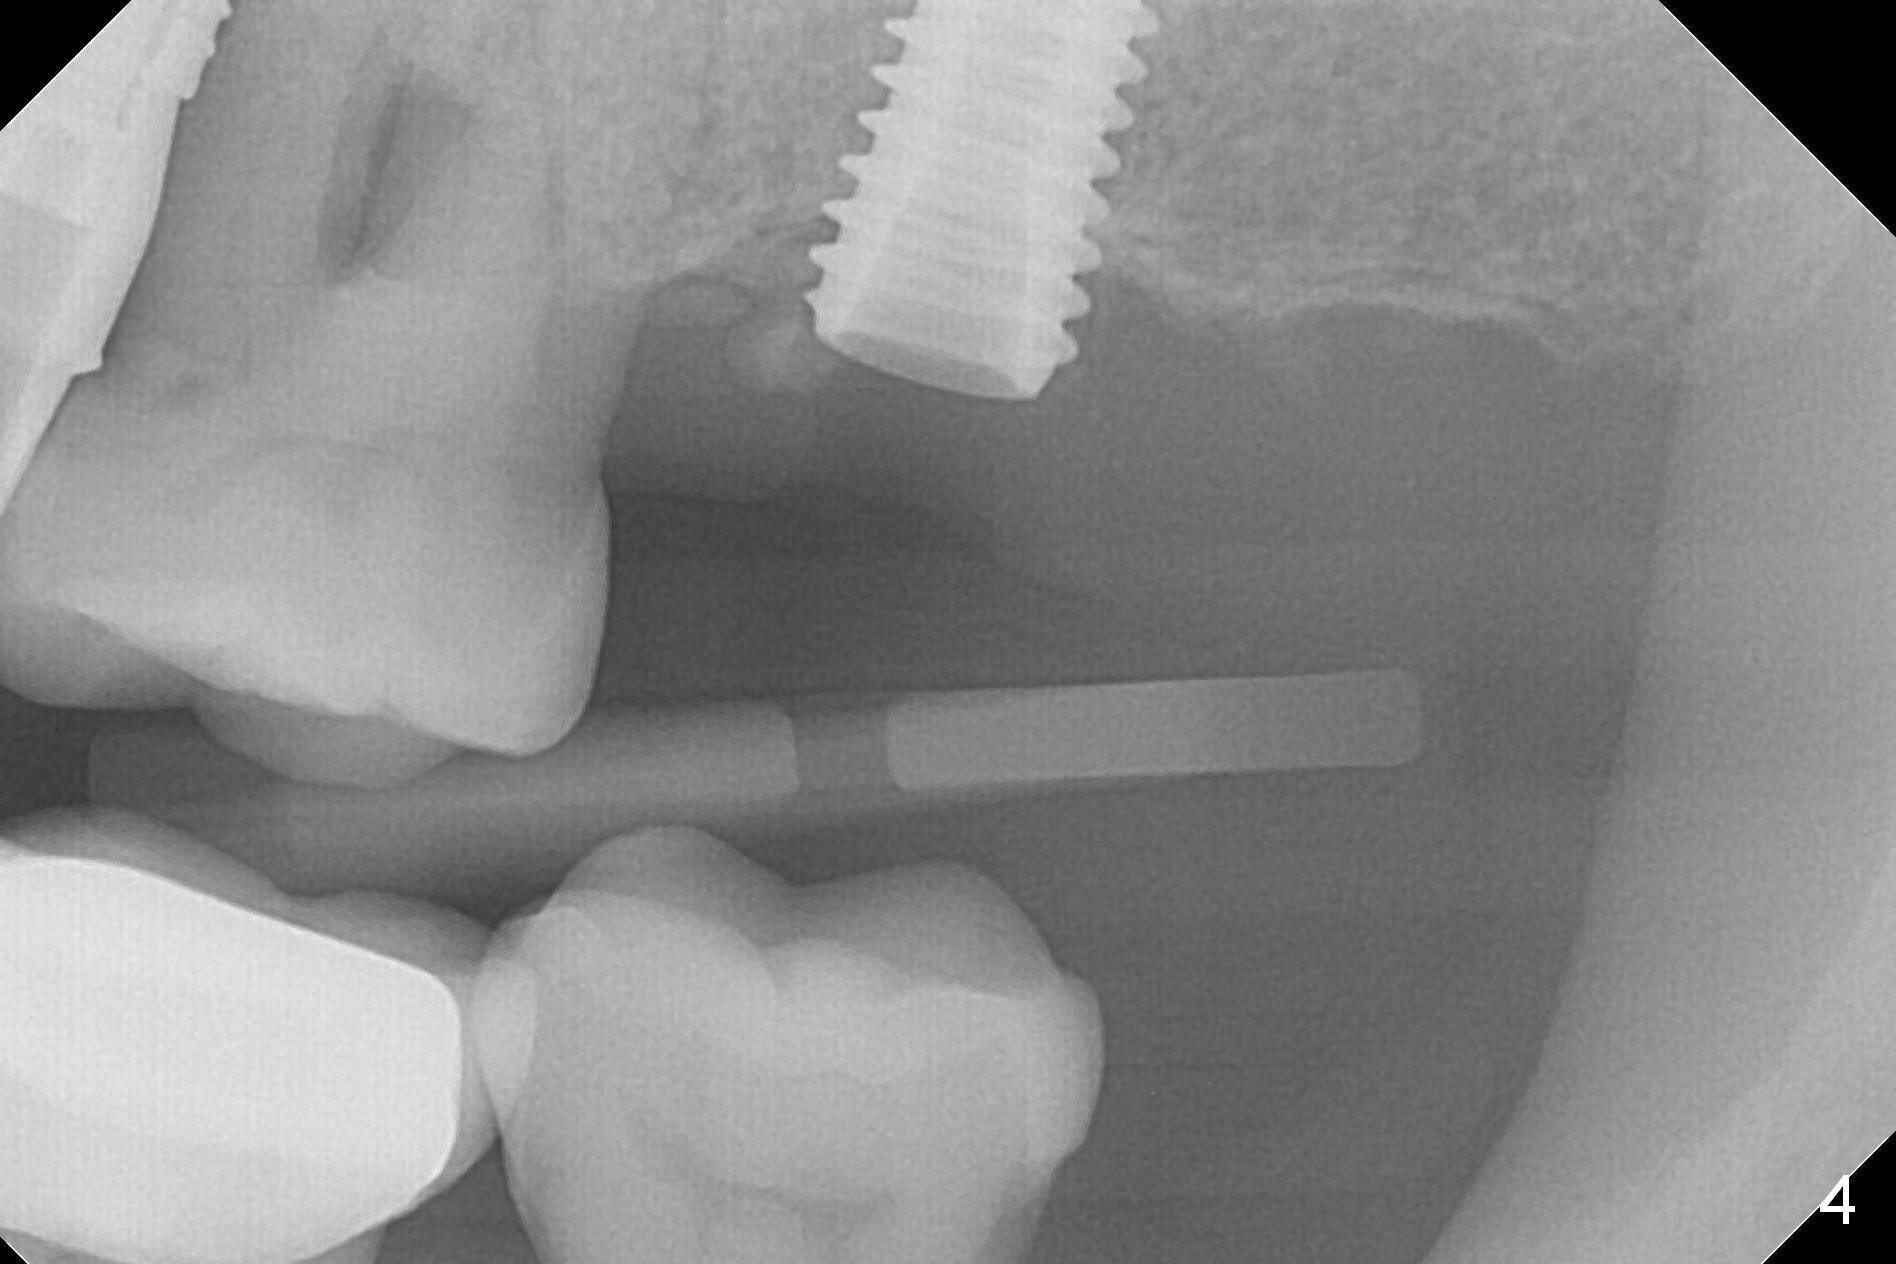

A 1.2 mm initial drill is used to start osteotomy at the site of #15 (Fig.1). After moving the osteotomy distally (with Lindamann bur), the osteotomy is enlarged by DIO Bone Expanders until 2.4/3.7 mm for 18 mm (gingival level) (Fig.2). Following the expander 3.0/4.4 mm, a 5x13 mm UF implant is placed supracrestal (Fig.3,4). After deepening the osteotomy with 3.8 mm drill for 3 mm, the implant is placed deeper by ~ 2 mm (Fig.5 arrow). Since the tooth #18 is supraerupted, a healing abutment (5.5x12(3) mm) is placed (Fig.6: H); the gingiva adapts to the abutment well. Suture is not necessary. The bone remains stable 2 and 4.5 months postop (Fig.7,8). Impression is taken. A crown is delivered nearly 6 months postop (08/07/2017). While there is minimal bone loss at #13 and 15 three years and 4 months post cementation, the tooth #14 and 18 are mobile (Fig.13,14, #13).